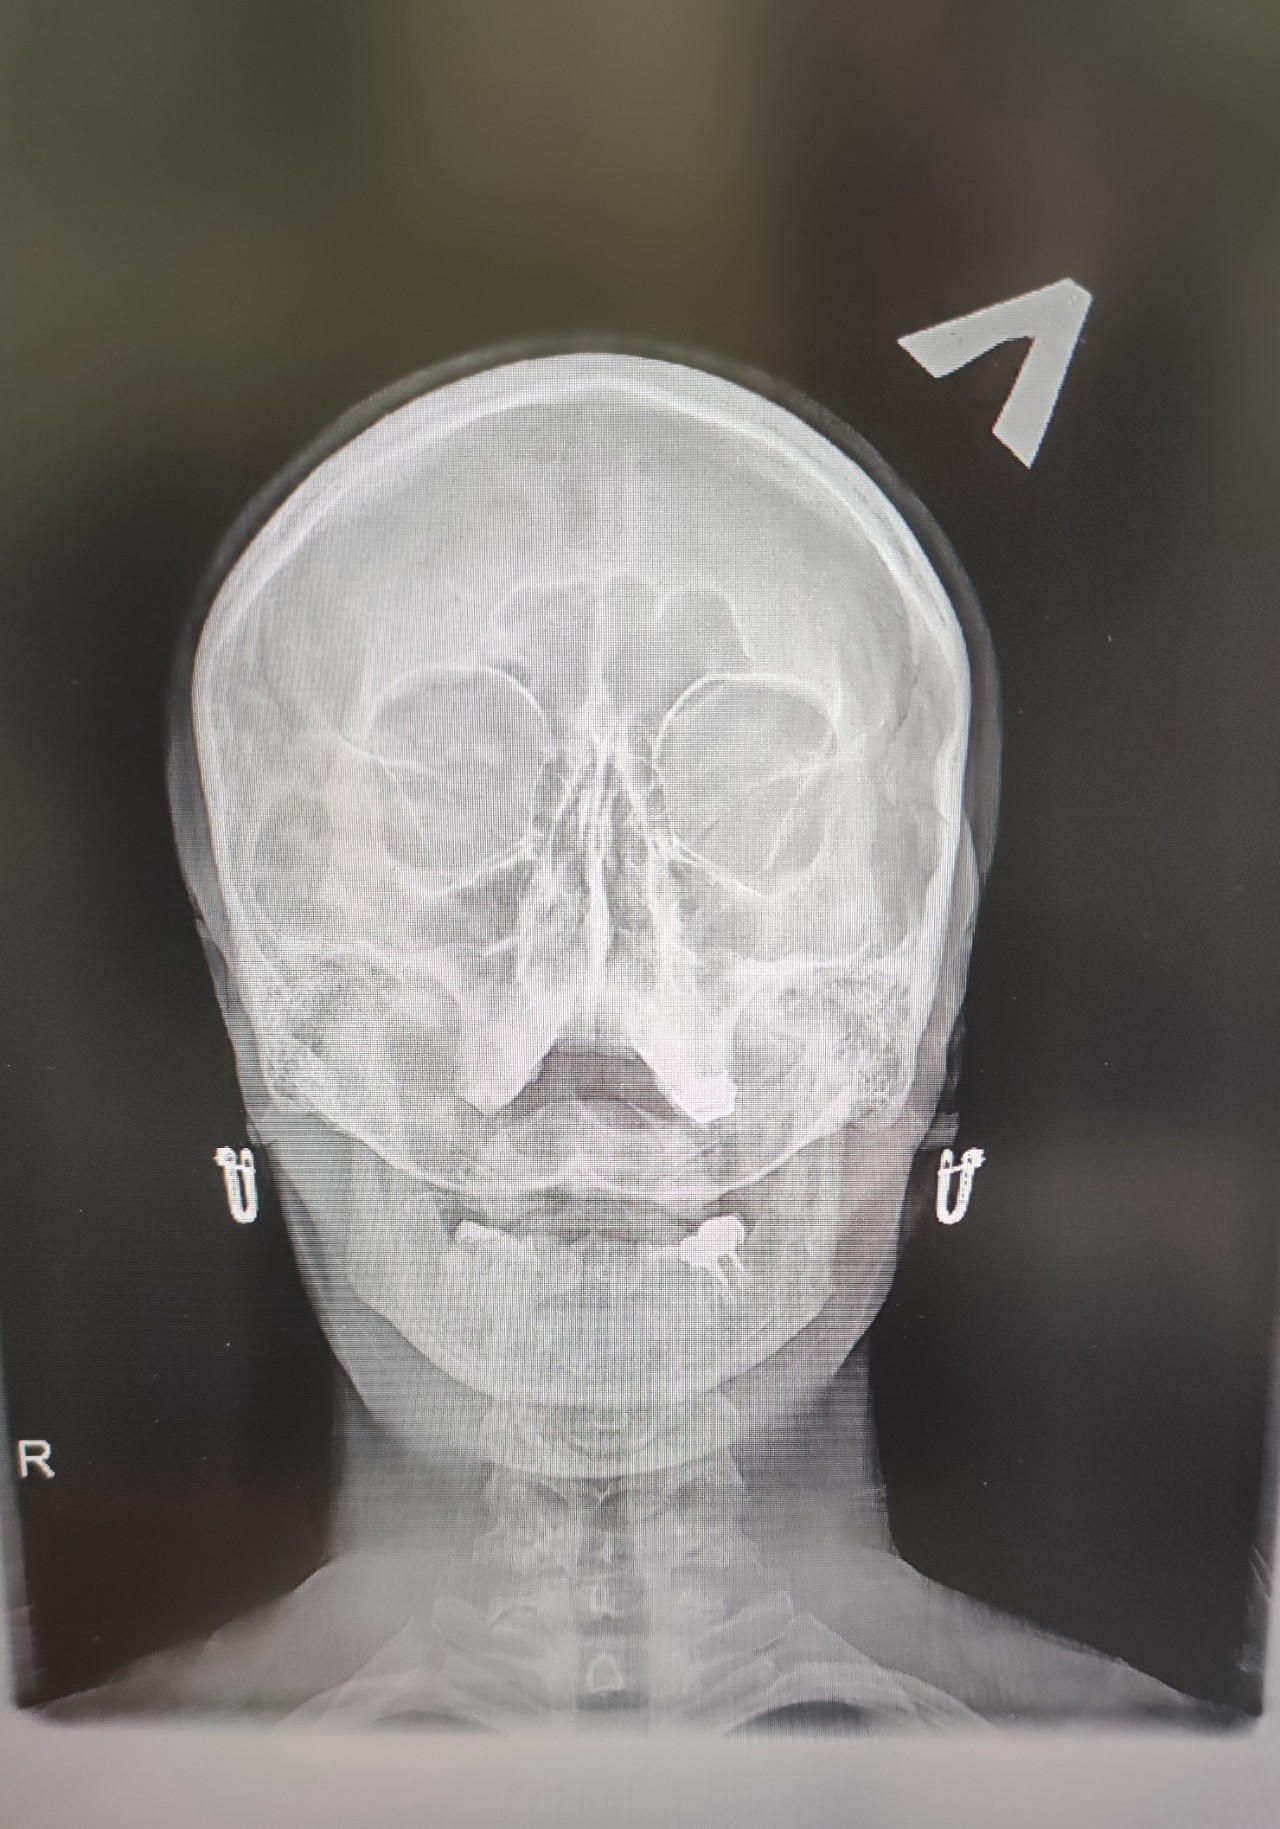

Вітаю, два дня назад была сильная головная боль без причины, после этого с левой ноздри начала течь прозрачная жидкость иногда с розоватым оттенком, сделали рентген сказали что нужно пробивать пазуху и все пройдет, может там на снимке видно ещё что-то, тольком не объяснили